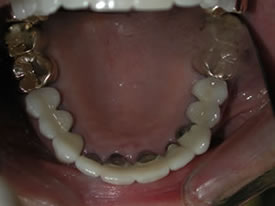

| Here's a close-up look at her upper arch (top

teeth) and lower arch (bottom teeth): |

Before